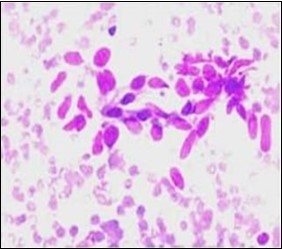

On gross examination, a tan coloured, gritty nodule, confined to the sternocleidomastoid muscle is delineated. Characteristically, smears obtained by fine needle aspiration cytology are composed of bland appearing, plump or normal fibroblasts and proliferating fibroblasts with an admixture of degenerative, atrophic skeletal muscle cells, giant myocytes with several nuclei, scattered, bare, bland nuclei or cells with fragmented, wispy cytoplasm and parallel aggregates of fibroblasts. The background is clear and devoid of cellular or nuclear debris. Sheets of spindle-shaped fibroblasts, atrophic muscle fibres and regenerating, multinucleated muscle giant cells are intermingled with the fibroblastic component 5, 6.

Figure 5.Fine needle aspiration cytology of fibromatosis colli exhibiting aggregates of spindle- shaped cells, plump fibroblasts, fibro-connective tissue fragments and a clear background with minimal red cell extravasation 12.